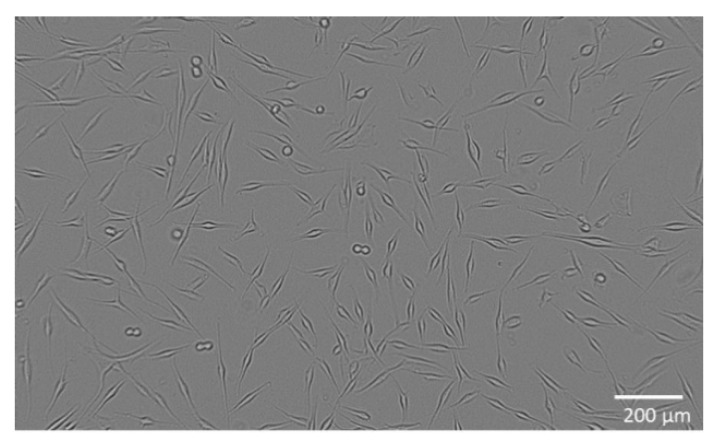

The combination of hemp and ginger extract has a promising inhibitory effect on melanoma cells [ref. 35]. Figure 1 shows the metabolic activity of WM-266-4 cells in the absence of extract and in the presence of extract at various concentrations (0.01–30.00 µg/mL). Treatment of WM-266-4 melanoma cells with hemp-ginger extract resulted in a significant decrease in metabolic activity in the presence of extract concentrations of 1.00 µg/mL and higher compared with the metabolic activity of melanoma cells in a medium without extract (control). The data were non-normally distributed and Levene’s test indicated equal variances (F = 0.995, p = 0.474). Therefore, the Kruskal-Wallis test was performed, which indicated a statistically significant difference in mean metabolic activity across concentrations (χ2 = 24.823, p = 0.003). The post hoc Dunn test confirmed significant differences between the mean metabolic activity of the control group (without extract) and the mean metabolic activity of the cells treated with extract of concentration 1.00 µg/mL and higher, as shown in Figure 1. The latter is also shown by the morphology of the cells in Figure 2. The images show the shape of the cells after application of the extract (1.00 µg/mL) (Figure 2b) and the shape of the cells in the control group (Figure 2a). Irregular cell shapes can be seen, indicating an apoptotic response.

The skin metastatic melanoma cell line WM-266-4 (ATCC® CRL1676™, Manassas, VA, USA) was purchased from American Type Culture Collection (ATCC, Manassas, VA, USA) and cultured in Eagle’s Minimum Essential Medium (EMEM, ATCC® 30-2003™, Manassas, VA, USA) containing 10 vol.% fetal bovine serum (FBS, ATCC® 30-2021™, Manassas, VA, USA) with addition of 0.02 vol.% MycoZap™ Plus-CL (Lonza, Portsmouth, NH, USA). The cells were incubated at 37 °C, 5% CO2, ≥90% RH and plated at a density of 2 × 104 viable cells per well in 96-well culture plates. The cells were cultured in a complete medium for 24 h to allow cell attachment (Figure 6). Normal human epidermal melanocytes (NHEM) (SI-104-05A, Taufkirchen, Germany) are primary cells and were grown in a complete medium: melanocyte growth medium (SI-135-500, Manassas, VA, USA). The cells were plated at a density of 1 × 104 viable cells per well in 96-well culture plates and cultured for 24 h in medium to allow cell attachment (Figure 7).

To analyse the metabolic activity of the cells, they were exposed to different concentrations of the extract (0.01–30.00 µg/mL) and incubated for 24 h, with five replicates performed. Control cells were not exposed to the extract but were cultured in the medium for the same time and under the same conditions. For cells’ metabolic activity measurement, a WST 8 Colorimetric Cell Viability Kit I (PromoKine, PromoCell, Heidelberg, Germany, EU) was used according to the manufacturer’s instructions. Absorbance (A) was measured spectrophotometrically at 570 nm (A570) (background A was measured at 630 nm (A630)) in pentaplicates for all samples. The percentage of the cells’ metabolic activity (MA) was calculated with the following equation:

where A represents the average value of absorbance calculated from five replicates. Additionally, cell morphology was observed with an inverted microscope (DM16000B, Leica) using a digital camera (DFC365 FX Leica, Lake City, IL, USA).